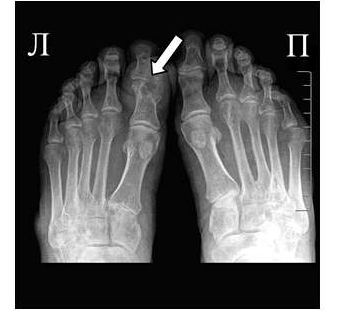

Эрозии при подагрическом артрите имеют округлую или овальную форму, часто со склеротическим ободком. Склеротический ободок вокруг внутрисуставного тофуса создает типичный для подагрического артрита симптом «пробойника» (см. рис. 1).

В отличие от ревматоидного артрита и полиостеоартроза ширина суставной щели при подагре обычно сохраняется в норме даже в поздних стадиях заболевания. Также для хронической стадии, в отличие от ревматоидного артрита, не характерен остеопороз. Таким образом, I плюснефаланговый сустав наиболее характерная локализация при подагрическом артрите.

Рис. 2 Симптом «пробойника» в головках плюсневых костей обеих стоп в сочетании с вальгусной девиацией I плюсне-фаланговых суставов

Эрозии часто обнаруживаются в верхней и медиальной части плюсневой головки и часто в сочетании с вальгусной девиацией суставов. Типичным является асимметричность изменений (рис. 2).